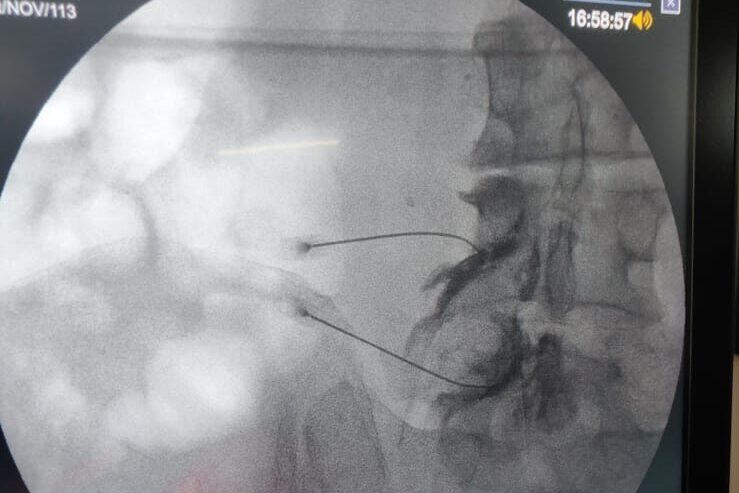

Our clinic is the first to offer world class comprehensive pain management services in Uttarakhand. All our procedures are : *Non surgical, *Painless, *Less than 1 hour duration, *Done under imaging guidance, *Performed by experienced professionals

- Transforaminal epidural lumbar/ thoracic/ cervical

- Caudal neuroplasty